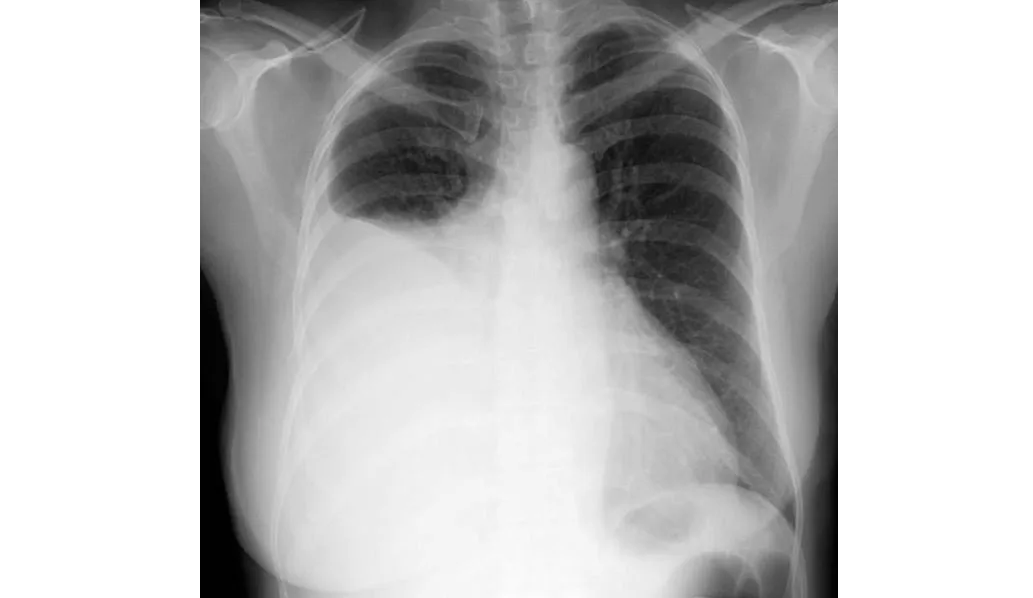

Farmacocinética de los antibióticos en derrames pleurales infectados.

En este estudio sobre farmacocinética de antibióticos realizado en pacientes con derrames pleurales infectados se encontró que los antibióticos de uso común, como amoxicilina, metronidazol, piperacilina-tazobactam y clindamicina, alcanzan niveles en el líquido pleural equivalentes a los de la sangre y por encima de la CIM para las bacterias que se sabe que causan infección pleural. La preocupación sobre la penetración de antibióticos de uso común en el espacio pleural infectado (excepto por la trimetroprima)  son infundadas. Thorax, 4 de julio de 2024.